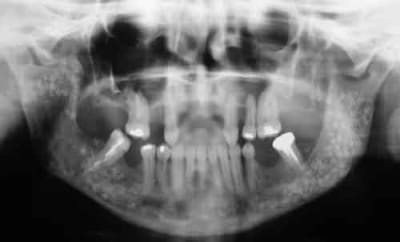

Femme de 40 ans. Aucun antécédent (notamment chirurgical) en dehors d'un DNID, d'un tabagisme modéré (5 paquets-année) et d'une surcharge pondérale. Consulte pour apparition progressive d'une volumineuse voussure dans les 2 vestibles inférieurs et d'une modification consécutive de la forme de la partie inférieure de son visage. A l'examen clinique : tuméfaction dure et fixée dans les 2 vestibules. Sensibilité (V3) normale. Gencive normale. Dents restantes non mobiles, vitales. Pas d'adénopathies palpables. Biologie non faite pour l'instant. Je vous joinds l'OTP et le scan. Diagnostic et options de traitement?

Cas clinique otp tlercd - Eugenol

La radio est petite mais ca donne envie de se lancer sur la trace d'un ameloblastome....pour commencer

Ce qui me gene un peu dans l histoire de l ameloblastome c qu il y en aurait un ds le sinus et un dans la mandibule en meme temps?

La cavité a la mandibule ca pourrait etre un gros kyste?

du coté de la dent incluse dans le ramus, on peut penser comme diagnostic probable a un kyste d'origine dentaire -image uniloculaire bordée sur son pourtour par une corticale bien individualisée et sur le scanner disparition de l'espace péricoronaire de la couronne avec continuité de toute la cavité.

diagnostic différentiel a faire avec d'autre lésions par ponction et anapat qui confirmeront ou non le diagnostic présomptif.

on a le choix entre pas mal de choses dont l'ameloblastome, le kyste multiloculaire, le kyste dentigère, la tumeur de Pindborg

je ne pense pas a l'ameloblastome, on n'a pas ici l'image caracteristique en "bulles de savon",on n'a pas de projection de petites cavités radioclaires en périphérie et pas de resorption des dents adjacentes qui restent vitales

le kyste multiloculaire montre plusieurs compartiments bien définis , ici l'origine dentaire est possible mais n'explique pas les images multiples derriere la molaire donc peu probable

on peut penser a une tumeur de Pindborg, les pourtours des cavités sont moins nettes et rondes que pour un améloblastome et de plus la tumeur a des bords irréguliers et une tendance à l'envahissement local qui semble confirmé par la disparition de la corticale supérieure sur la partie coronaire de la mandibule

Moi, j'opte pour des améloblastomes bilatéraux ou de multiples kystes kératinisés .

tumeur odontogène épithéliale calcifiée (Pindborg)

localisée à la mandibule...image radiographique claire en rapport avec une dent incluse qui est refoulée...il existe ici de multiples géodes...présence de calcifications dans la clarté...

Bref, en ce qui concerne ce cas (assez récent), je vous livre le raisonnement qui a été le notre : probables kystes péricoronnaires sur les dents incluses (il n'y a pas de dents "surnuméraires"...). Décision d'abord chirurgical pour énucléation des 3 kystes (les ponctions ne "marchent" pas dans ces lésions) et examens anatomopathologiques extemporanés pour décider, en per-opératoire, de la conduite à tenir (photo 1).

Diagnotic extemporané : kératokystes (!). Les dents incluses se sont donc avérées être un piège diagnostic! Le traitement s'est de ce fait contenté d'un curetage appuyé des paroies osseuses, conservation des 2 nerfs dentaires et, en raison de la taille des kystes mandibulaires et du risque de fracture post-opératoire, nous avons y avons associé une greffe (hydroxyapatite + os autologue (crête illiaque) + PRP) au niveau mandibulaire uniquement (photos 2 et 3)et blocage intremaxillaire pendant 15 jours.

Les suites ont été simples, la reminéralisation des kystes est actuellement en cours (photo 4) et la sensibilité des V3 est normale.